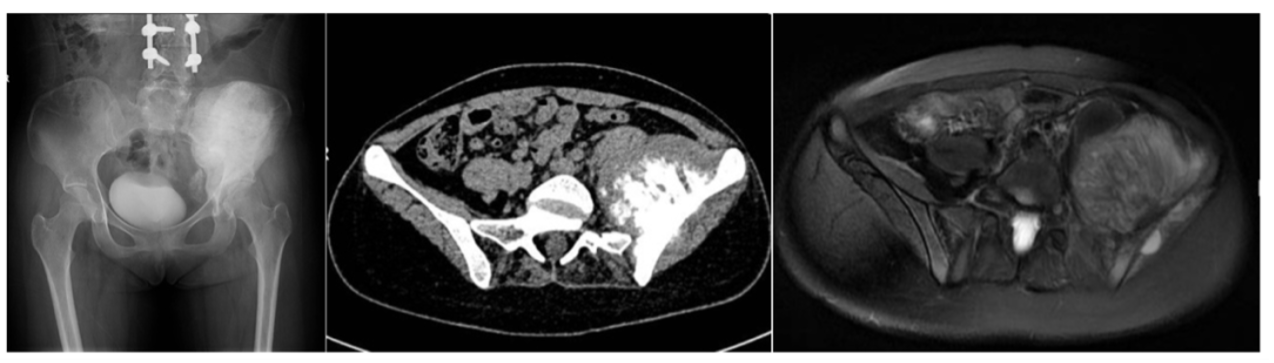

来自江苏的20岁小瑶同学,2022年12月因“腹部肿痛加重不适,无法下地行走”入院的。患者既往有脊柱侧弯手术病史